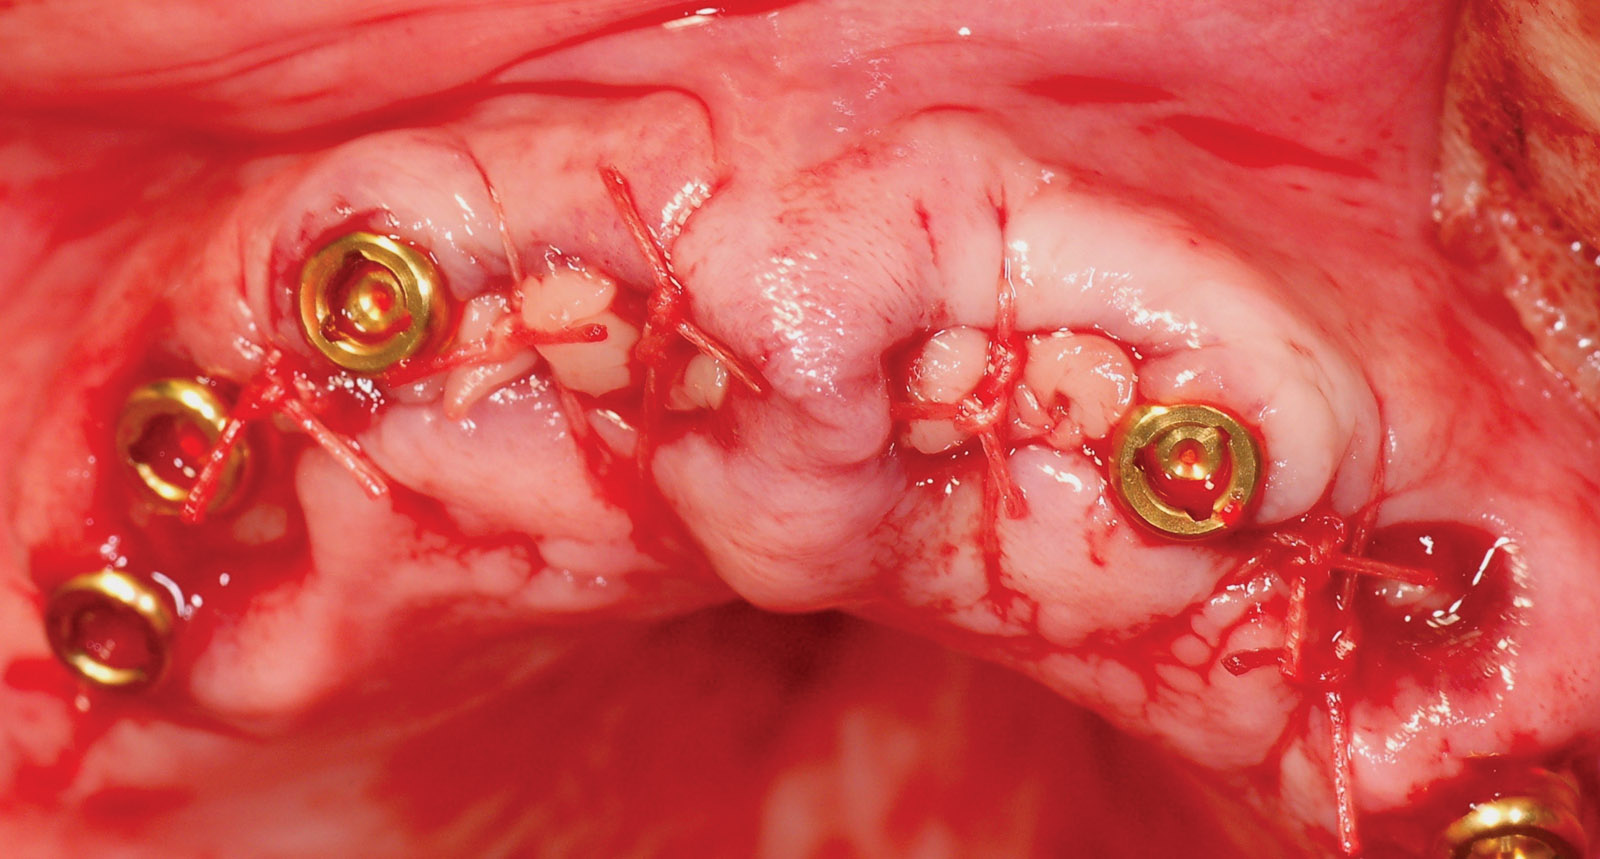

Axiom Bone Level implants (Oct 21) 18 October, 2021 Figure 1: Profile view Figure 2: Intra-oral view of remaining maxillary teeth Figure 4: A CBCT scan of the upper jaw was taken to accurately assess the anatomy, bone volume and trajectory of the alveolar ridges Figure 5: Inadequate bone below the maxillary sinuses Figure 6: Immediate extraction sockets Figure 7: Implants placed, and Locator abutments attached Figure 8: Metal housing on Locator abutments just before pick-up in the denture Figure 9: Metal housing precisely secured in the denture Figure 10: Denture fitted immediately following implant placement Figure 3: The OPG radiograph confirmed the absence of any pathology in both jaws and presence of large maxillary sinuses Figure 12: Following three weeks of undisturbed healing Figure 13: Following 12 weeks of complete healing Figure 14: Profile view immediately following implant treatment